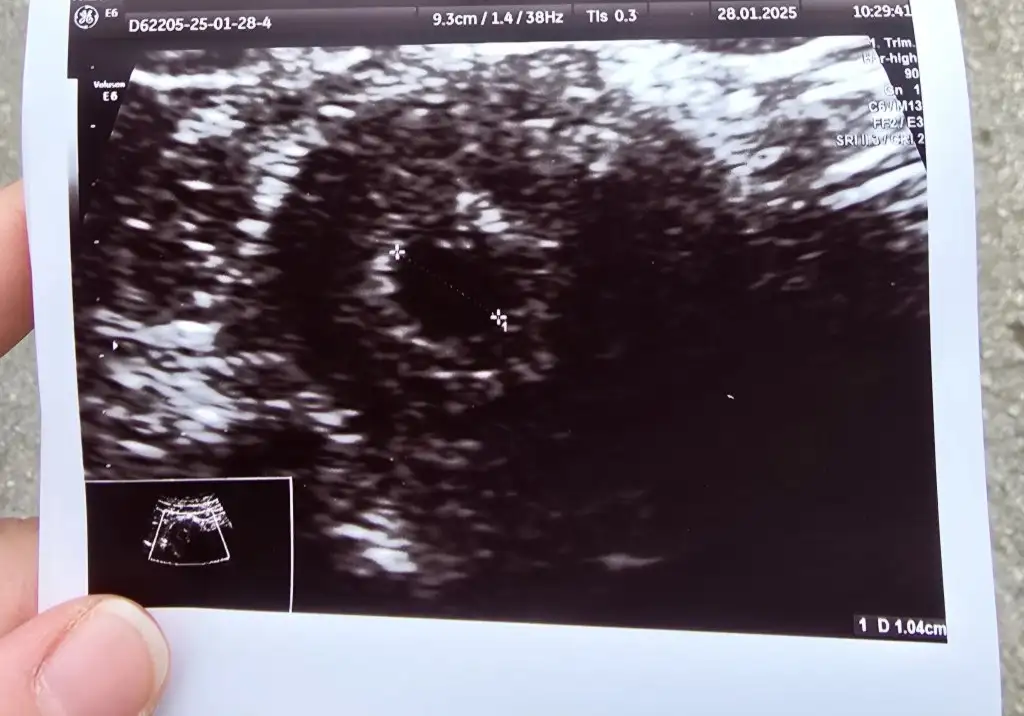

28 ocakta keseyi gördüm .

Bana 5 haftalık tam dedi Eki Görüntüle 3537754